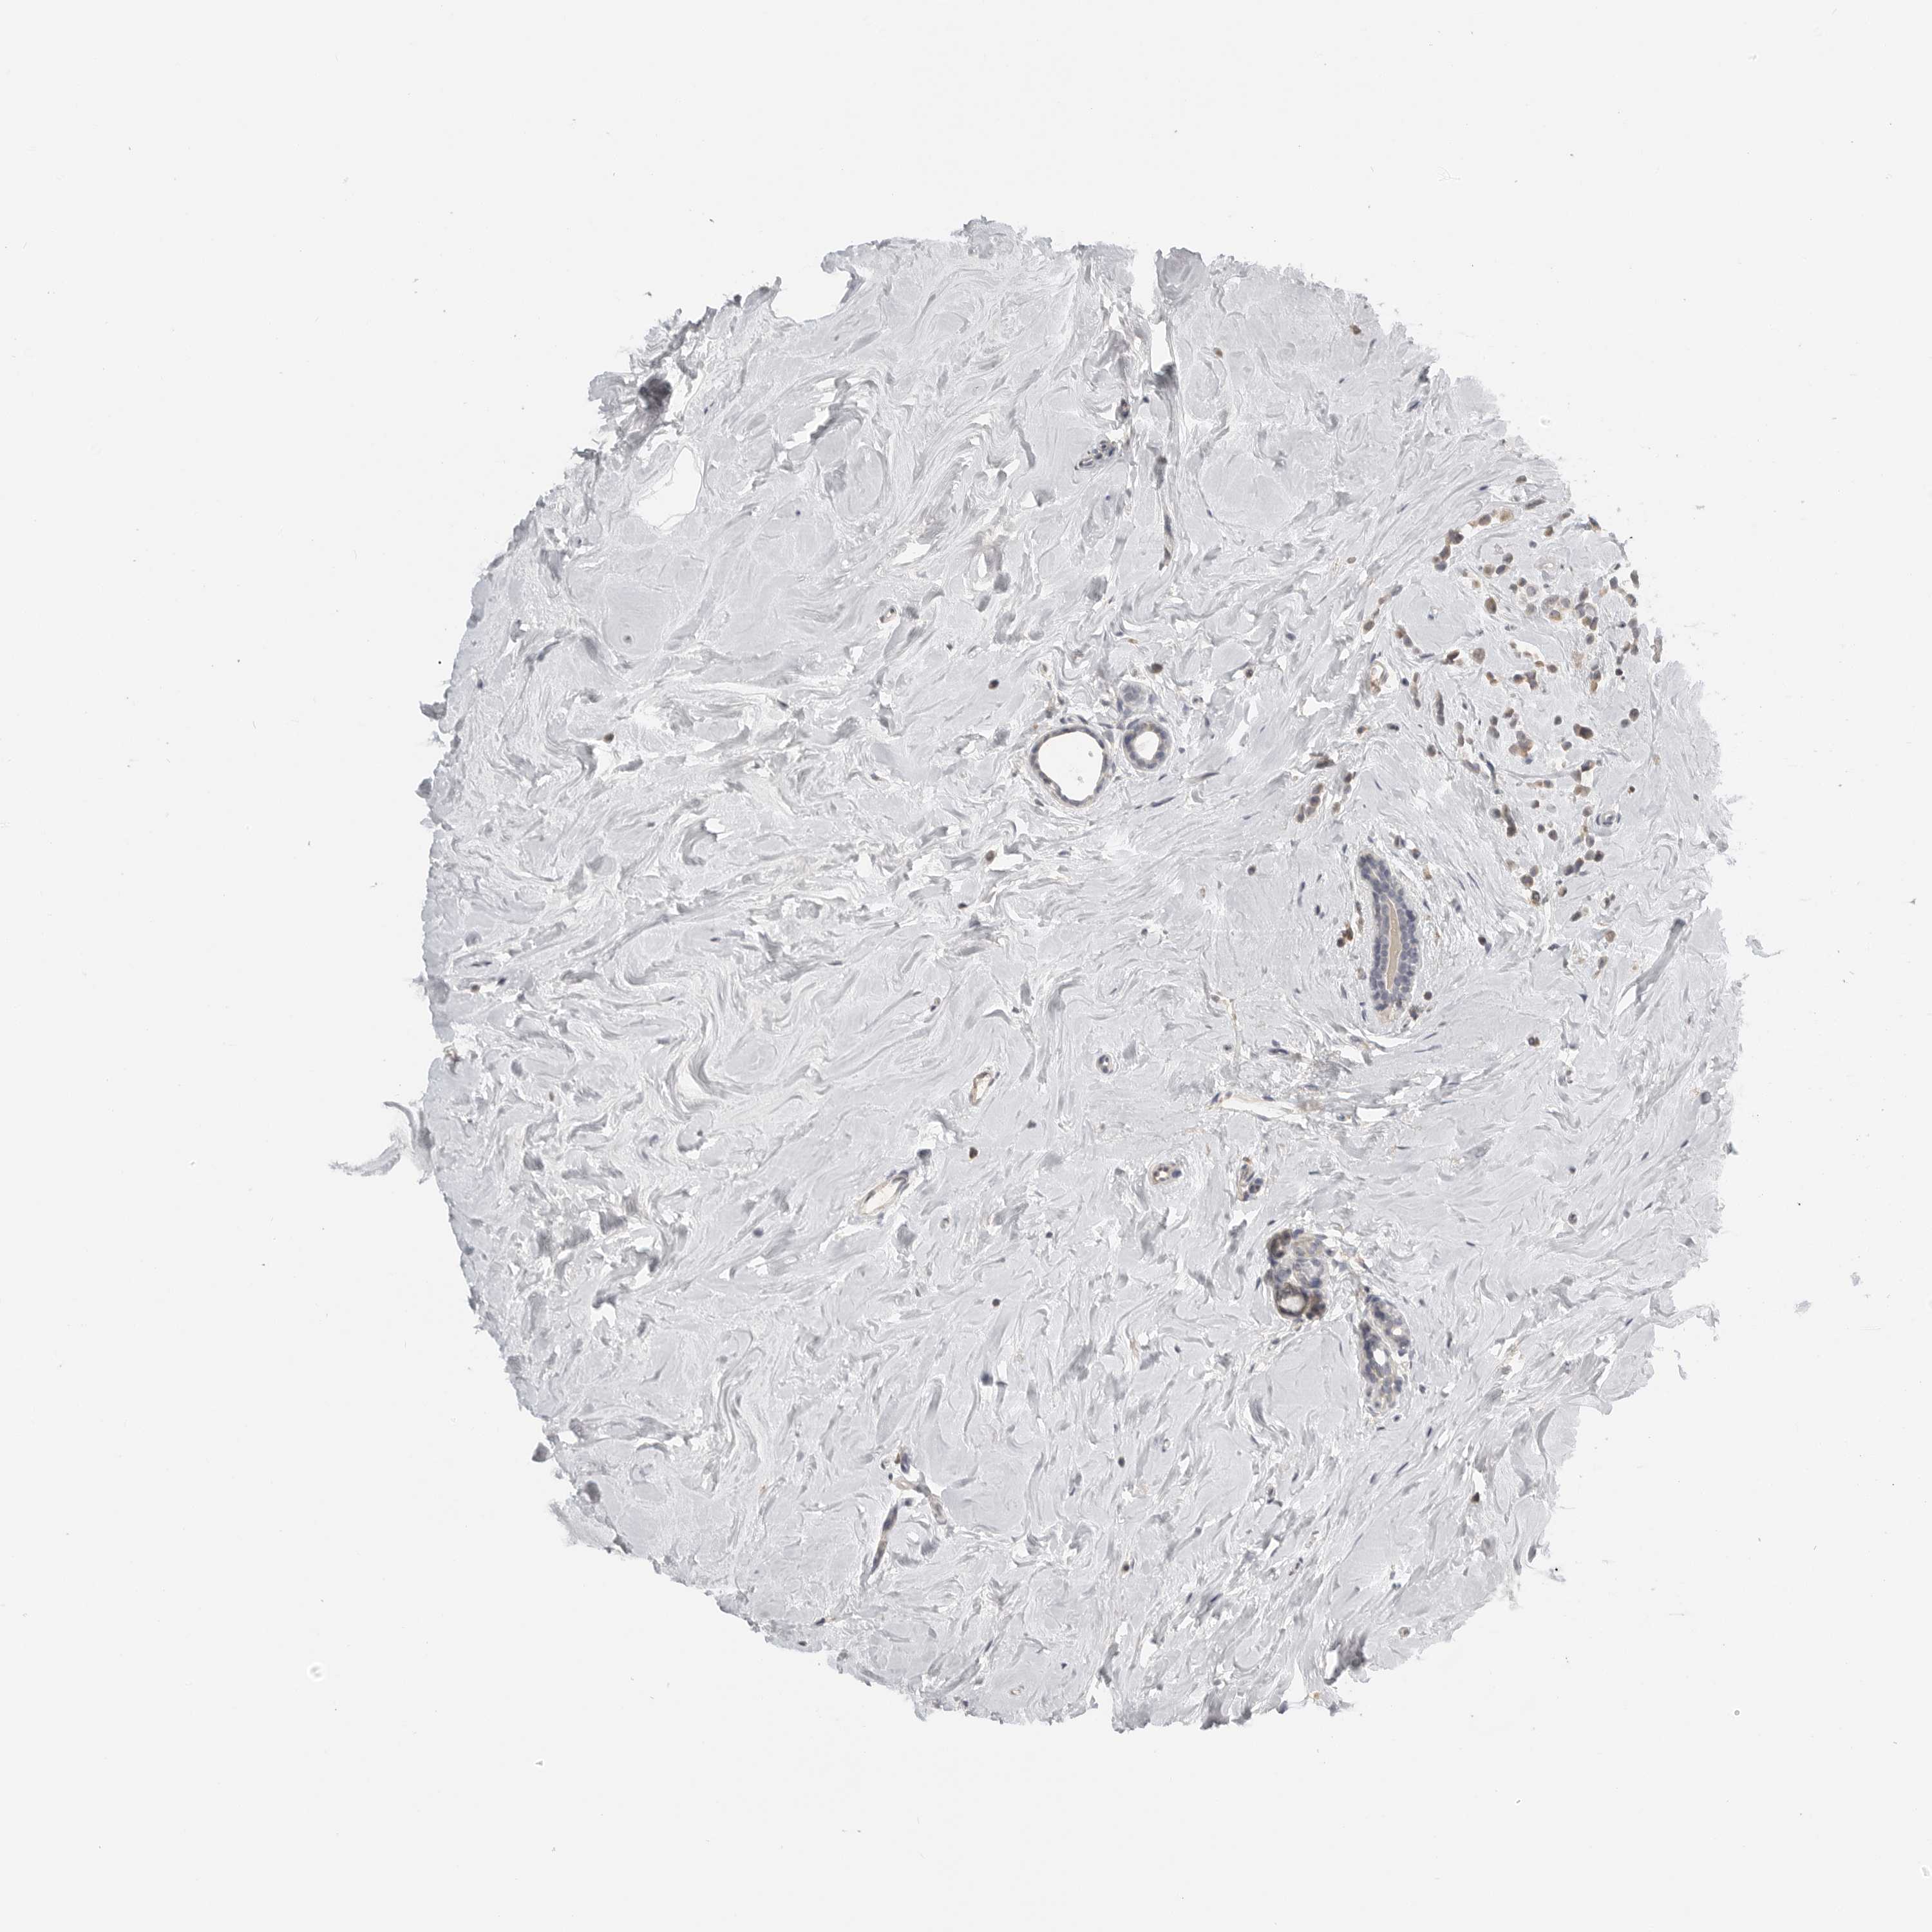

CANCER BREAST CANCER Show tissue menu

BRCA TCGA BRCA VALIDATION PROTEIN EXPRESSION

Breast cancer

Human cancer

RXFP3 is not prognostic in Breast Invasive Carcinoma (TCGA)